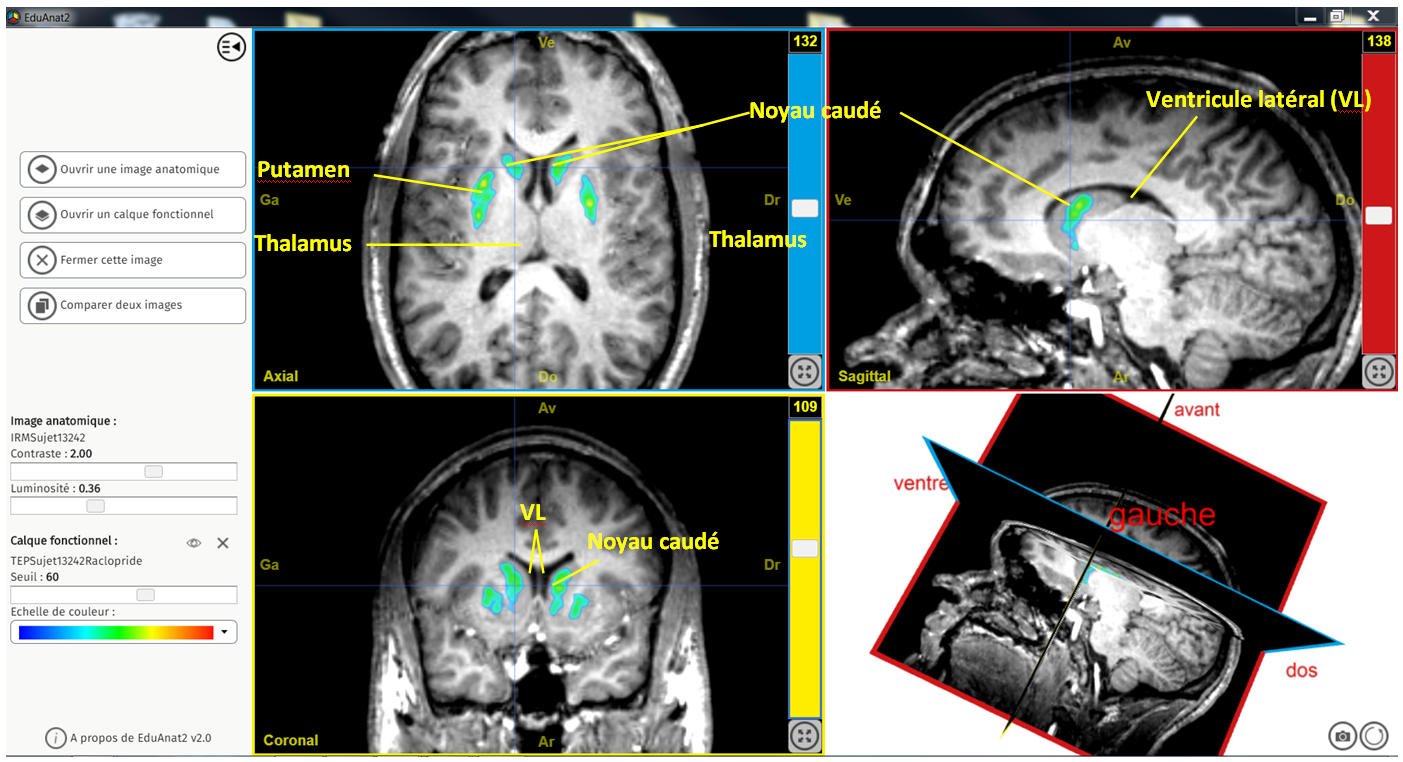

Capture 3 plans de coupe vue striatum